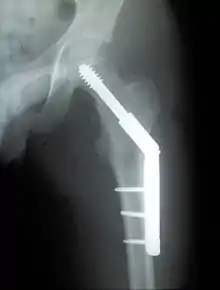

Closed reduction may not be satisfactory and open reduction then becomes necessary.[42] The use of open reduction has been reported as 8-13% among pertrochanteric fractures, and 52% among intertrochanteric fractures.[43] Both intertrochanteric and pertrochanteric fractures may be treated by a dynamic hip screw and plate, or an intramedullary rod.[42]

The fracture typically takes 3–6 months to heal. As it is only common in elderly, removal of the dynamic hip screw is usually not recommended to avoid unnecessary risk of second operation and the increased risk of re-fracture after implant removal. The most common cause for hip fractures in the elderly is osteoporosis; if this is the case, treatment of the osteoporosis can well reduce the risk of further fracture. Only young patients tend to consider having it removed; the implant may function as a stress riser, increasing the risk of a break if another accident occurs.